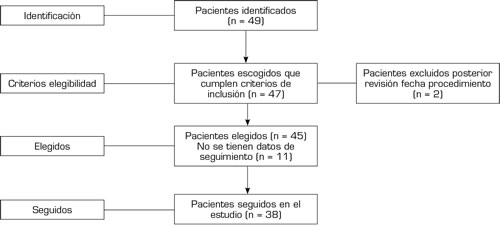

El 93 % (n = 35) de los pacientes llevados a bloqueo cluneal presentaron un EVA severo (mayor a 7) previo al procedimiento. El 28 % (n = 11) de los pacientes presentaron en el postbloqueo inmediato una disminución del dolor con un EVA menor de 6; en el primer control el 57 % (n = 22) conservaron la mejoría del dolor y el 10 % (n = 4) había retornado a su estado basal de dolor. Sin embargo, para el segundo control el 10 % (n = 4) de los pacientes no presentaron cambios en la intensidad del dolor de acuerdo con la valoración realizada previamente al procedimiento y el 78,9 % (n = 30) conservaba mejoría en la intensidad del dolor comparado con la EVA aplicada previo a bloqueo (Figura 3).

Fig. 3. Diagrama de caja y bigotes de la intensidad del dolor en cada momento. Momento 0: Previo a bloqueo el 93 % de los pacientes llevados a bloqueo cluneal presentaron un EVA severo (mayor a 7). Momento 1: inmediato al bloqueo, el 28 % de los pacientes presentaron una supresión del dolor con un EVA menor a 6. Momento 2 (primer control con media de 81 días [± 67]) el 57 % conservaron la mejoría del dolor, para el Momento 3 (segundo control post-intervención con media de 267 días (± 135,5) el 78,9 % conservaba mejoría en la intensidad del dolor.

El tiempo de realización de primer, segundo y tercer momento está comprendido entre 81 (± 67) y 267 días (± 135,5); después del bloqueo la intensidad del dolor en el primer momento fue 3, segundo momento 4, y tercer momento 6 (Tabla IV) evaluados con test de Wilcoxon con un valor (p < 0,001).